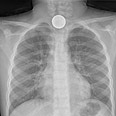

בחדר המיון סיפר אדם שבלע מטבע וצילום רנטגן שנערך לו הראה היכן בדיוק הוא תקוע. אדם הורדם והוכנס לחדר ניתוח שם הוצא המטבע מגרונו בעזרת מלקחיים זעירות.

חצי שקל בוושט. מזל שלא בקנה

באדיבות בי"ח וולפסון